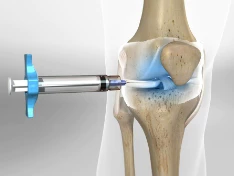

관절염은 이러한 관절 내부의 연골 파괴와 염증으로 인해, 일상 생활에서의 움직임에 큰 불편함을 초래할 수 있습니다. 이 질환은 조절된 관리와 치료가 필요하며, 적절한 관절 보호 및 염증 관리가 필수적입니다.

관절염의 종류와 원인은 다양하며, 진단과 치료는 종류에 따라 달라집니다. 따라서 관절염에 대한 이해와 관리가 중요하며, 올바른 치료 및 예방 조치를 통해 삶의 질을 향상시킬 수 있습니다.